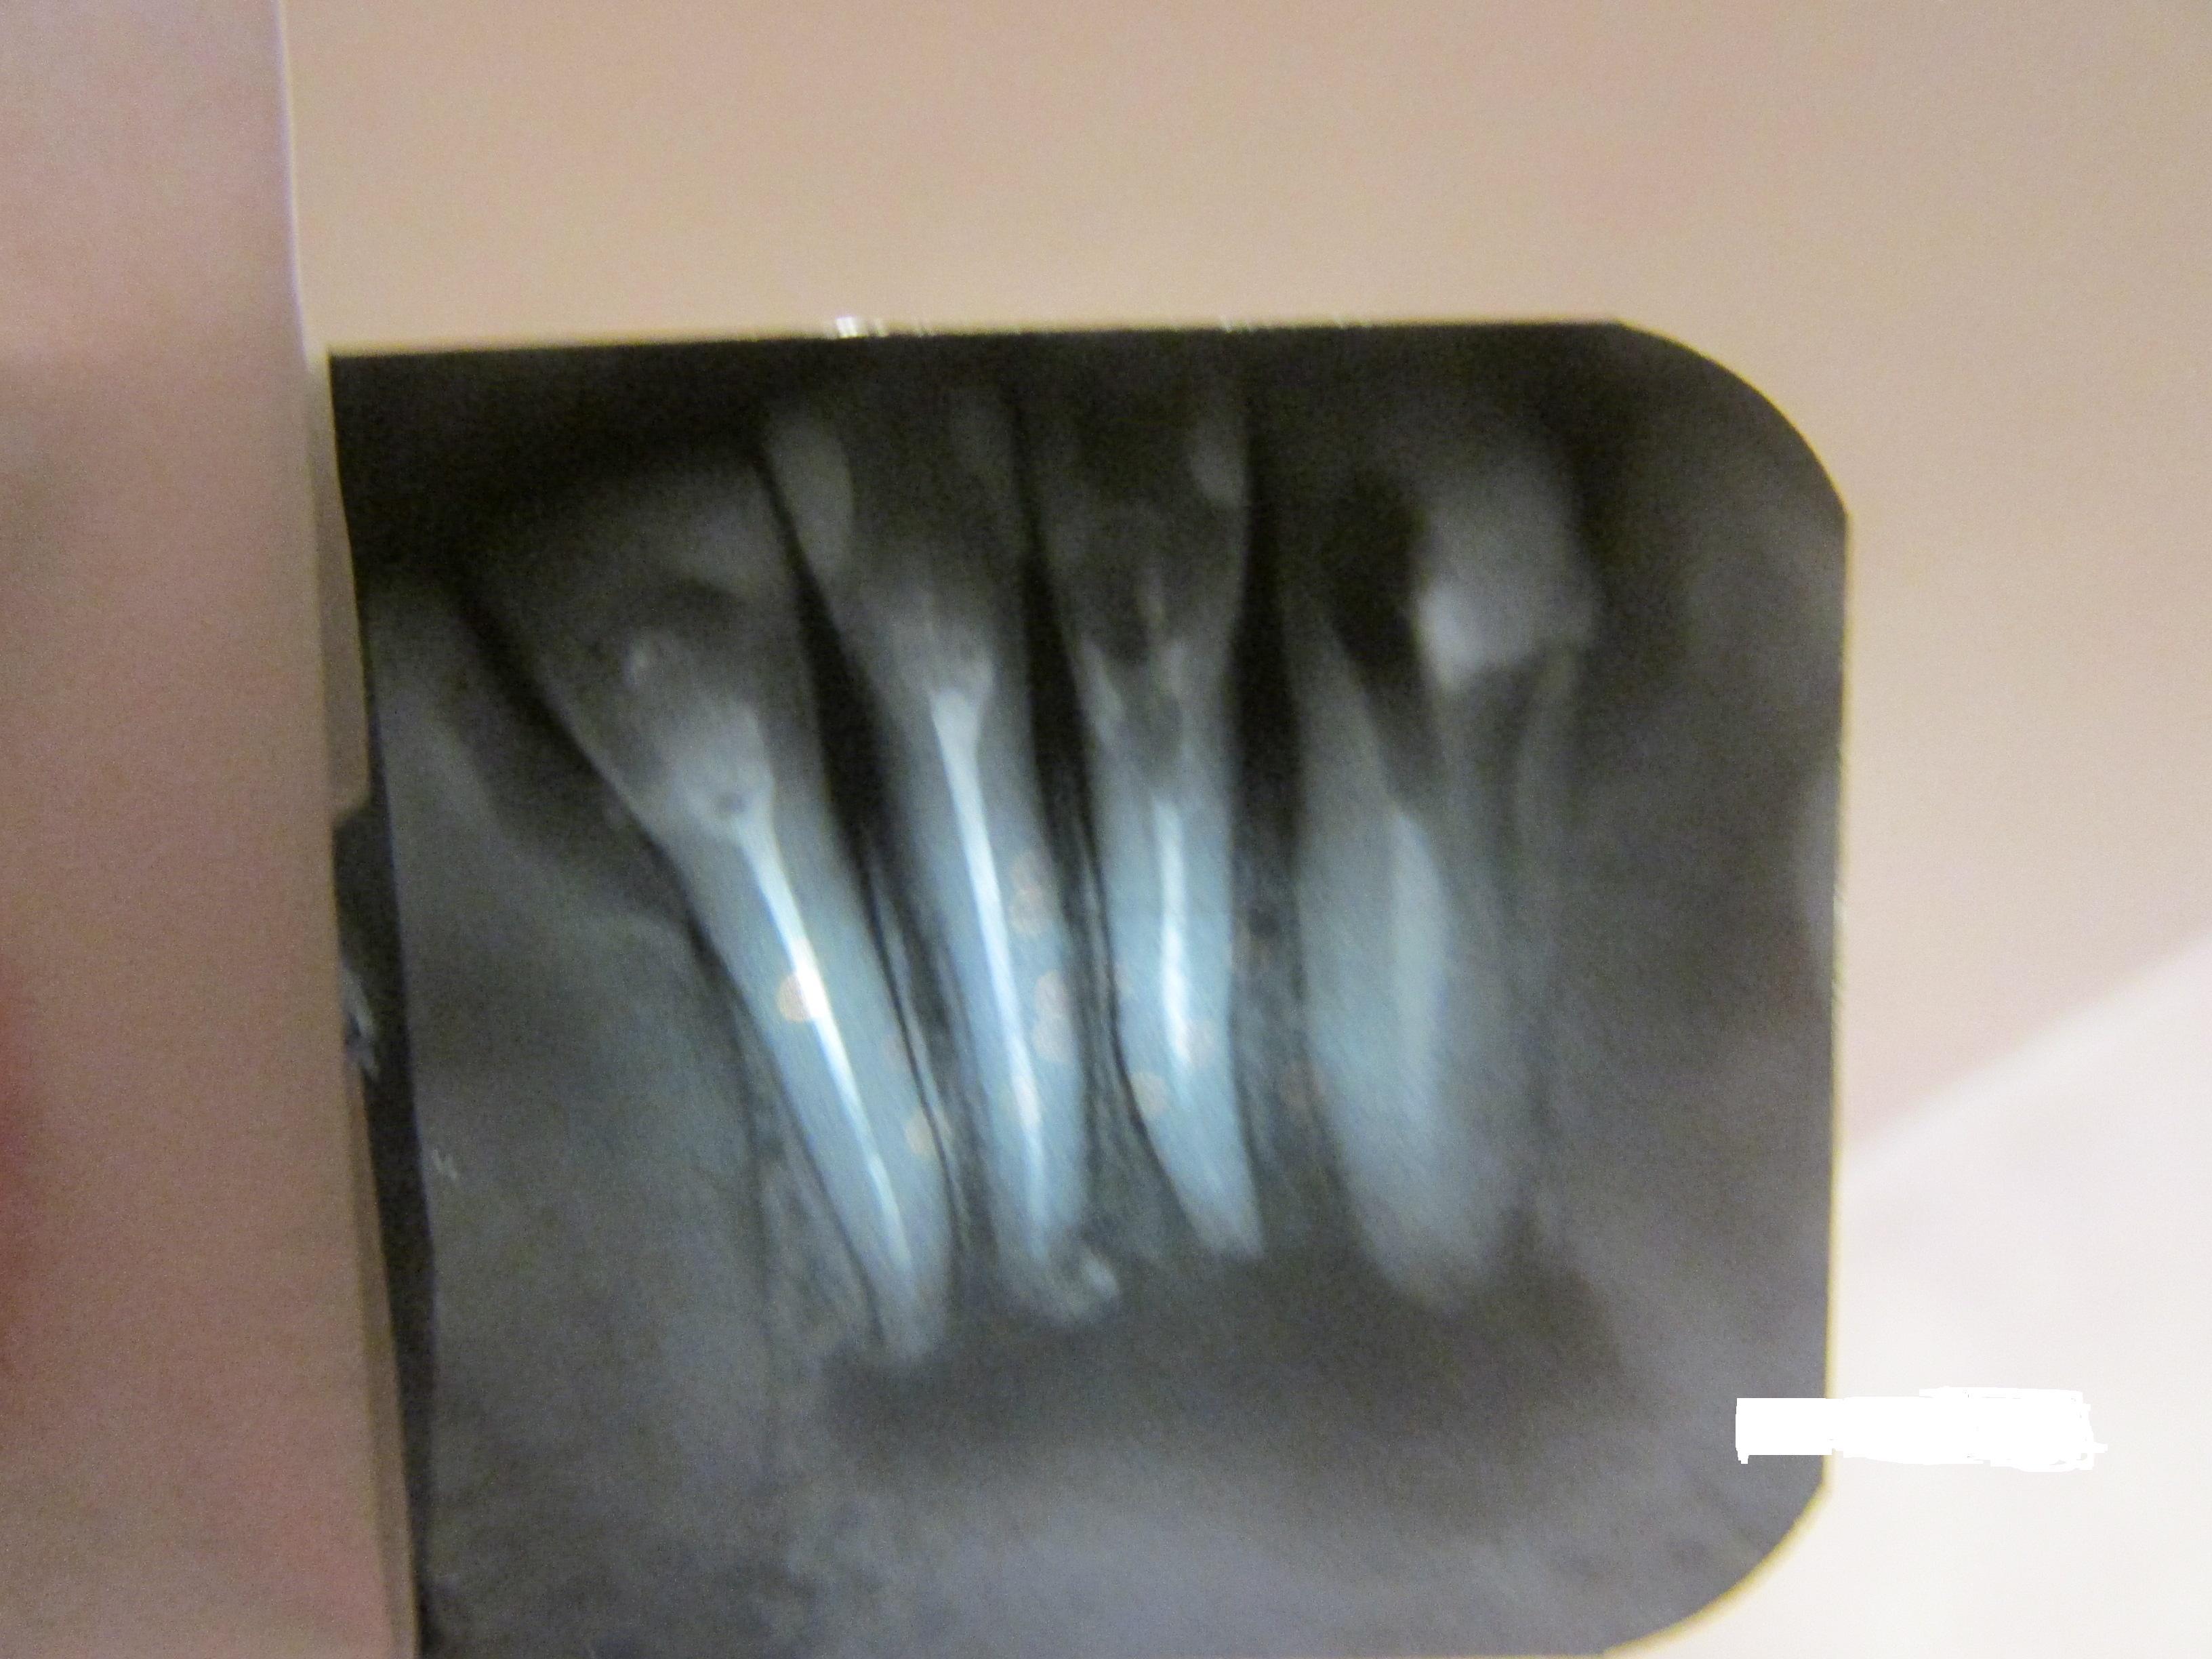

Здравствуйте, подскажите пожалуйста, можно спасти зубы? Спасибо.

Откровенно говоря, сложная ситуация и по всем показаниям зубы удаляются. Но если вы готовы рискнуть, то есть долго и упорно лечить и при этом гарантий не будет никаких, то можно попробовать, при этом подвижность зубов не должна быть.